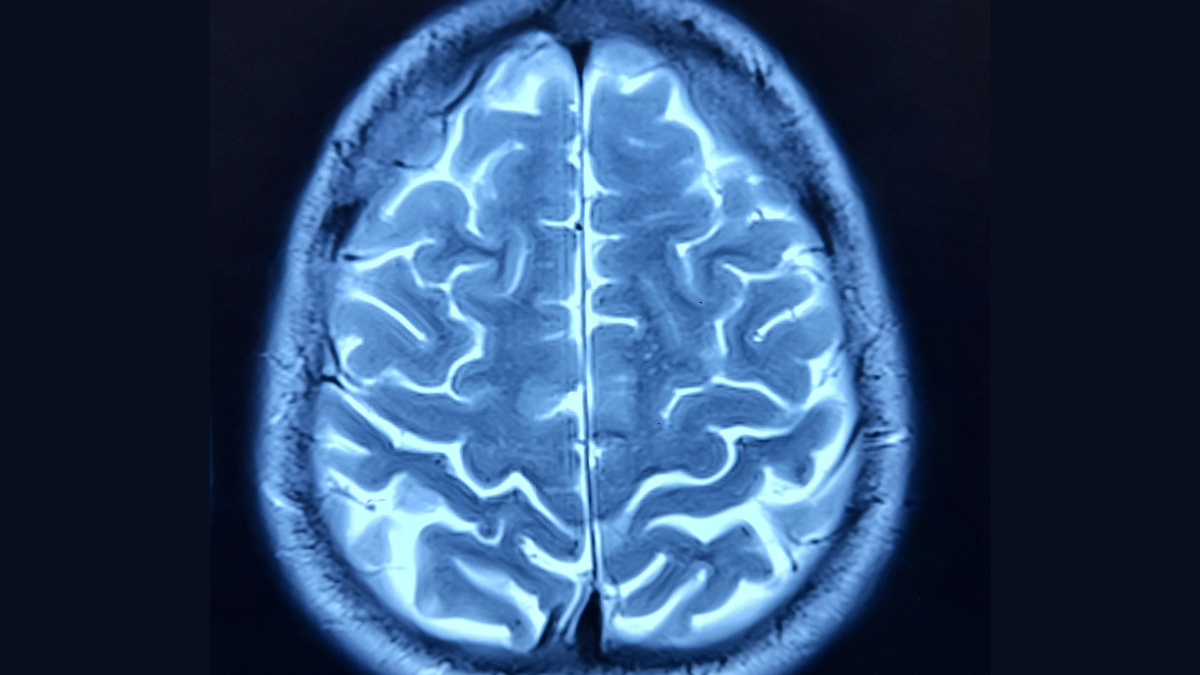

In the study, a team of international researchers developed ways to measure brain ageing using advanced brain clocks based on deep learning of brain networks. This study involved a diverse dataset of 5,306 participants from 15 countries, including Latin American and Caribbean (LAC) nations and non-LAC countries. By analysing data from functional magnetic resonance imaging (fMRI) and electroencephalography (EEG), the researchers quantified brain age gaps in healthy individuals and those with neurodegenerative conditions such as mild cognitive impairment (MCI), Alzheimer's disease, and frontotemporal lobe degeneration (FTLD).